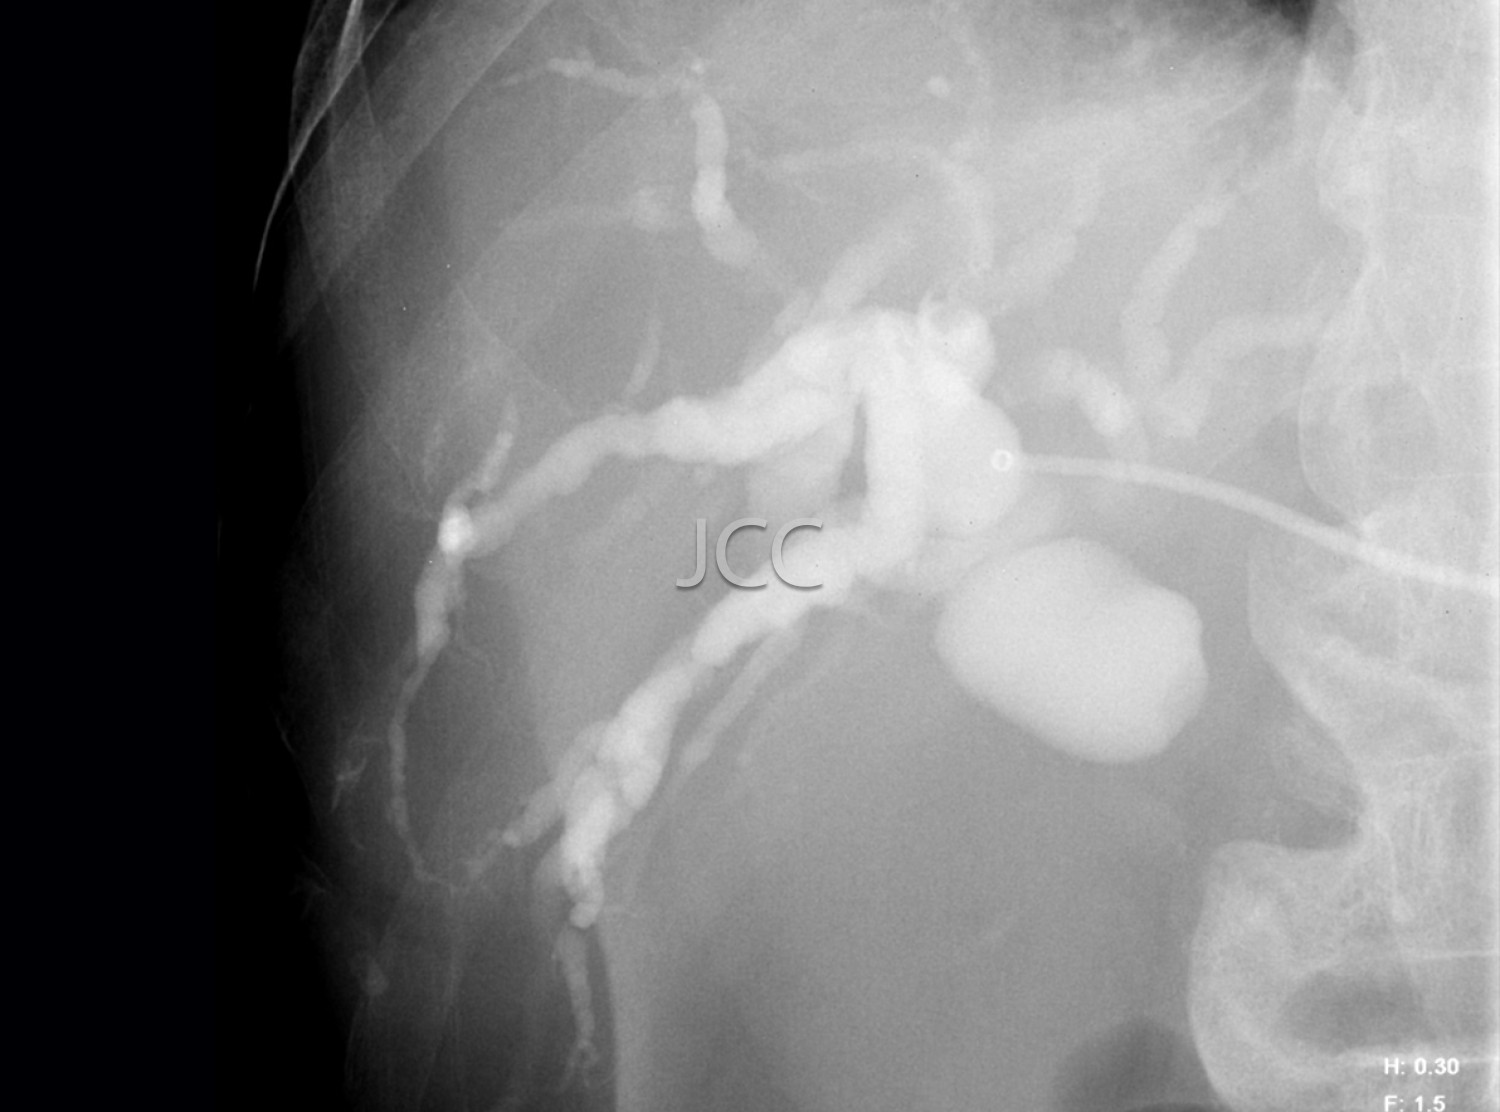

Radiologia de Intervenção - Drenagem Biliar

• O Paciente deverá estar em jejum 4 horas.